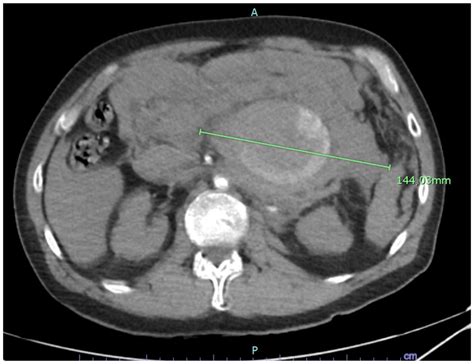

Computed Tomography (CT) Scan: Provides detailed cross-sectional images of the abdomen. It is often used to confirm the presence of an aneurysm and assess its size and location.